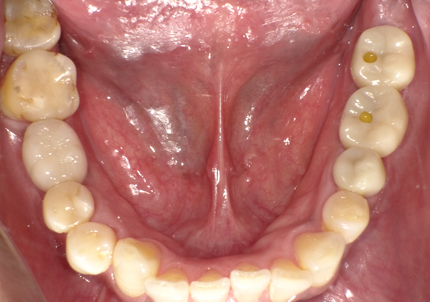

1.初診時口腔内写真(2014年6月)

2.治療終了(2016年6月)

・上顎補綴物再製

・右下2本インプラント

・左下ジルコニアクラウンブリッジ